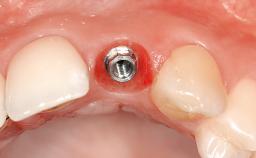

An 80-year-old female patient was referred to clinic for rehabilitation of her dentition. The patient’s medical history revealed no significant findings that would preclude routine dental and oral surgical procedures. She reported no drug allergies and was currently taking no prescription medications.

Her chief complaint was her inability to masticate efficiently due to the recent loss of her mandibular second premolars and first molars bilaterally. She expressed a desire for fixed prostheses in the shortest possible time due to her advanced age, requesting that replacement teeth should look as natural as possible. She was otherwise comfortable and not experiencing any symptoms from her teeth.